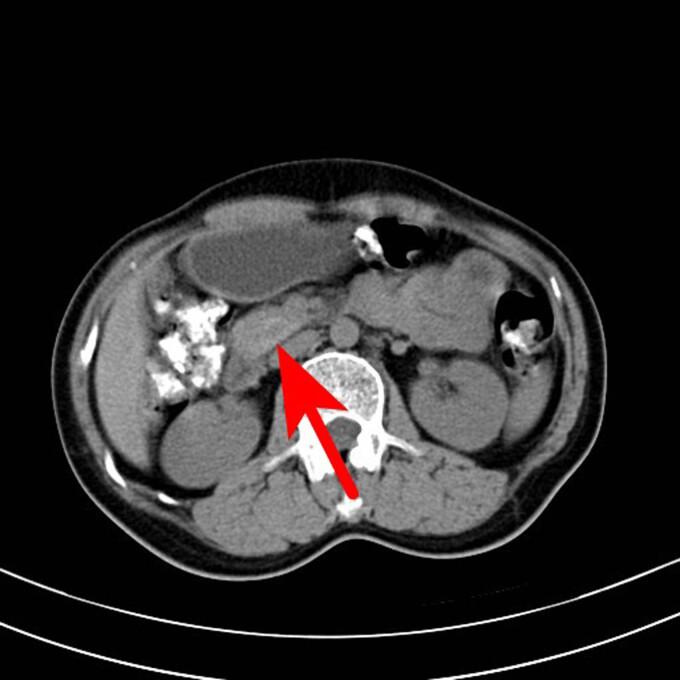

Ectopic thyroid is a rare malformation induced by a migration defect in the developing gland during embryogenesis. In 90% of cases, the ectopic thyroid is located in the lingual region, whereas it is extremely rare in the abdominal cavity, particularly in the pancreas. A 50-year-old female patient presented to the Taizhou First People's Hospital with a complaint of recurrent mid-lower abdominal pain and diarrhea for approximately a month. The abdominal computed tomography scan revealed a space-occupying lesion with abundant blood supply in the head of the pancreas during the consultation. This led to the suspicion of a neuroendocrine tumor. The doctor considered that this lesion in the head of the pancreas could be responsible for the patient's incontinence. A laparoscopic pancreaticoduodenectomy was performed after relevant tests were undertaken and contraindications were ruled out. The patient was diagnosed with ectopic thyroid of the pancreas through postoperative pathology. Ectopic thyroid can be considered in middle-aged and elderly women who present with a mass with abundant blood supply and an unknown diagnosis. Subsequent treatments should be decided after fine-needle aspiration cytology.